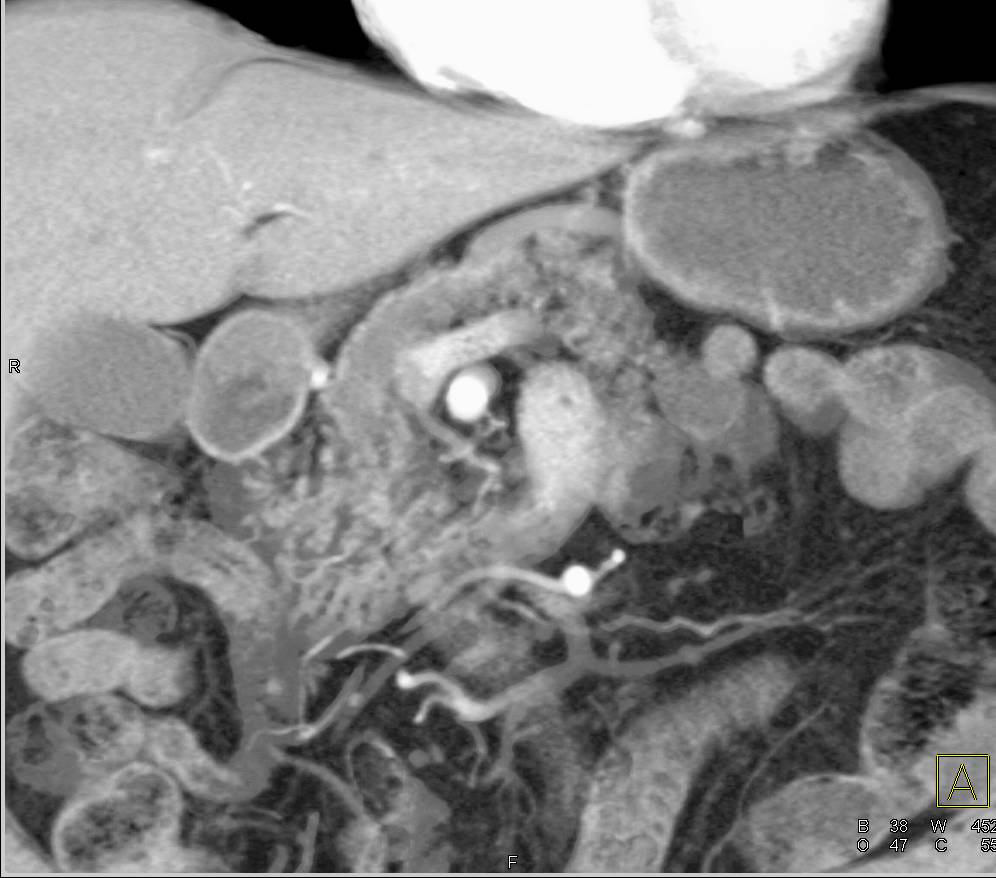

Acute Pancreatitis with Inflammation of Duodenum and Small Bowel Mesentery